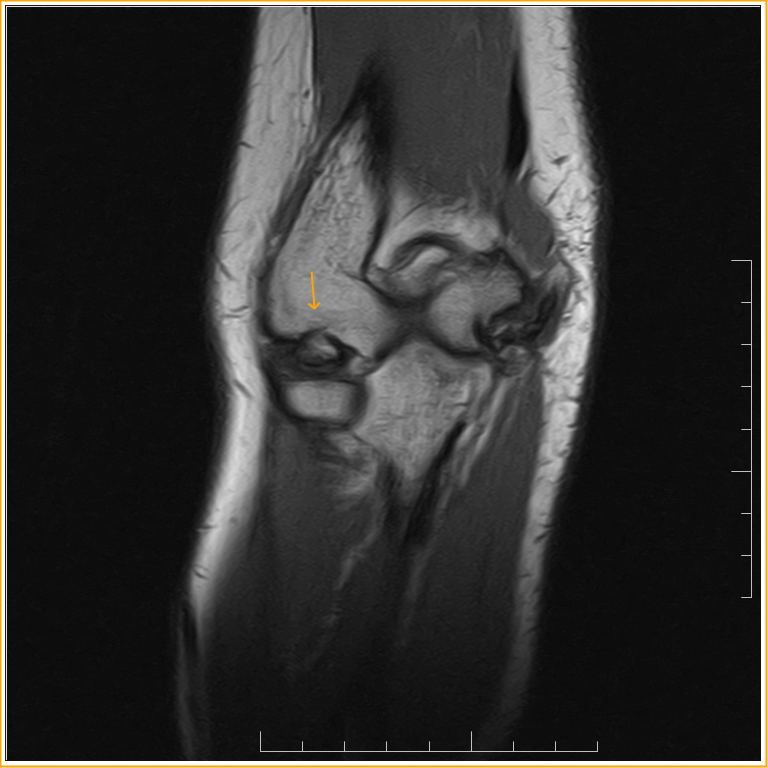

From radiopaedia.org